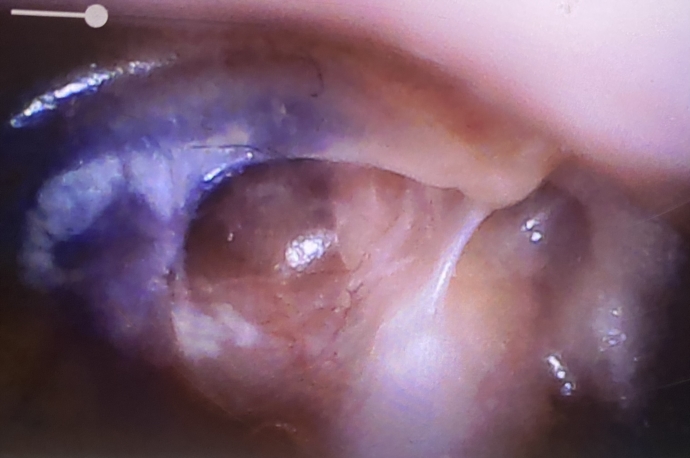

Hey can anyone take a look at these pictures and advise please? Ive got a complicated history with regards to problems with my left ear. As a child I had repeated infections / glue ear which lead to permanent hearing loss. I had multiple operations done to fit grommets and then an operation to remove a cholesteatoma and treat mastoiditis (mastoidectomy). I was 16 turning 17 when this last operation was done, I'm 35 now. At the time the mastoidectomy was done the consultant advised it was the worst one he had seen and it could have lead to me having TB, the infection was travelling to my brain.

Since then I've done fairly well, I have a couple of ear infections a year and numerous perforations but nothing like I used to, everything healed well eventually, it doesn't really get a wax build up, but I've been struggling a lot this last 12 months with middle ear fluid / infections. I bought an endoscope camera I could use to take pictures of my ear canal with during lockdown, so i could send pictures to the doctors surgery electronically rather than having to go in in person, I really struggle with anxiety / agoraphobia without the pandemic on top. Ive always had the odd nerve pains since my teens from my left ear and the operations, but I'm in a lot of pain currently. Ive already had 3 middle ear infections this year, this last one, I had a course of antibiotics for around 4 weeks ago but it doesn't seem to have done anything, its getting worse. I went to the doctors in person after the antibiotics didn't work as the pain had increased and they could see the fluid and the redness / irritated ear canal but they cant give me more of the same antibiotics (amoxicillin) because I will end up becoming immune to them helping and the second line ones they usually give I cant have as they are contraindicated with my other medication. They organised a referral back to ENT for me and gave me a nasal steroid spray to try and relax the swelling in my Eustacian tube and cocodamol to manage the pain, but my symptoms are getting worse.

The last two days I have had watery discharge from my ear canal, and since last night I have lost what is left of my hearing in that ear, it just feels completely full / blocked. I have ringing / buzzing / tinitus every time I speak and feel dizzy whenever I stand up it honestly feels like there's something behind the ear drum pressing on everything. On the previous pictures taken with the endoscope you could see air bubbles within the fluid behind my ear drum, on the latest picture there is no air bubbles now, the fluid is thicker and not as see through as it was before. I guess I'm looking for some advice, I don't want to ring the doctors again tomorrow and take up resources when an ENT referral has already been done but I feel shocking with it. The antibiotics cleared up my temperature, I havent got a temp anymore, but still have -

There does seem to be a lump on the right hand side behind the ear drum, could this be blocking the fluid draining or is this lump normal ear anatomy?